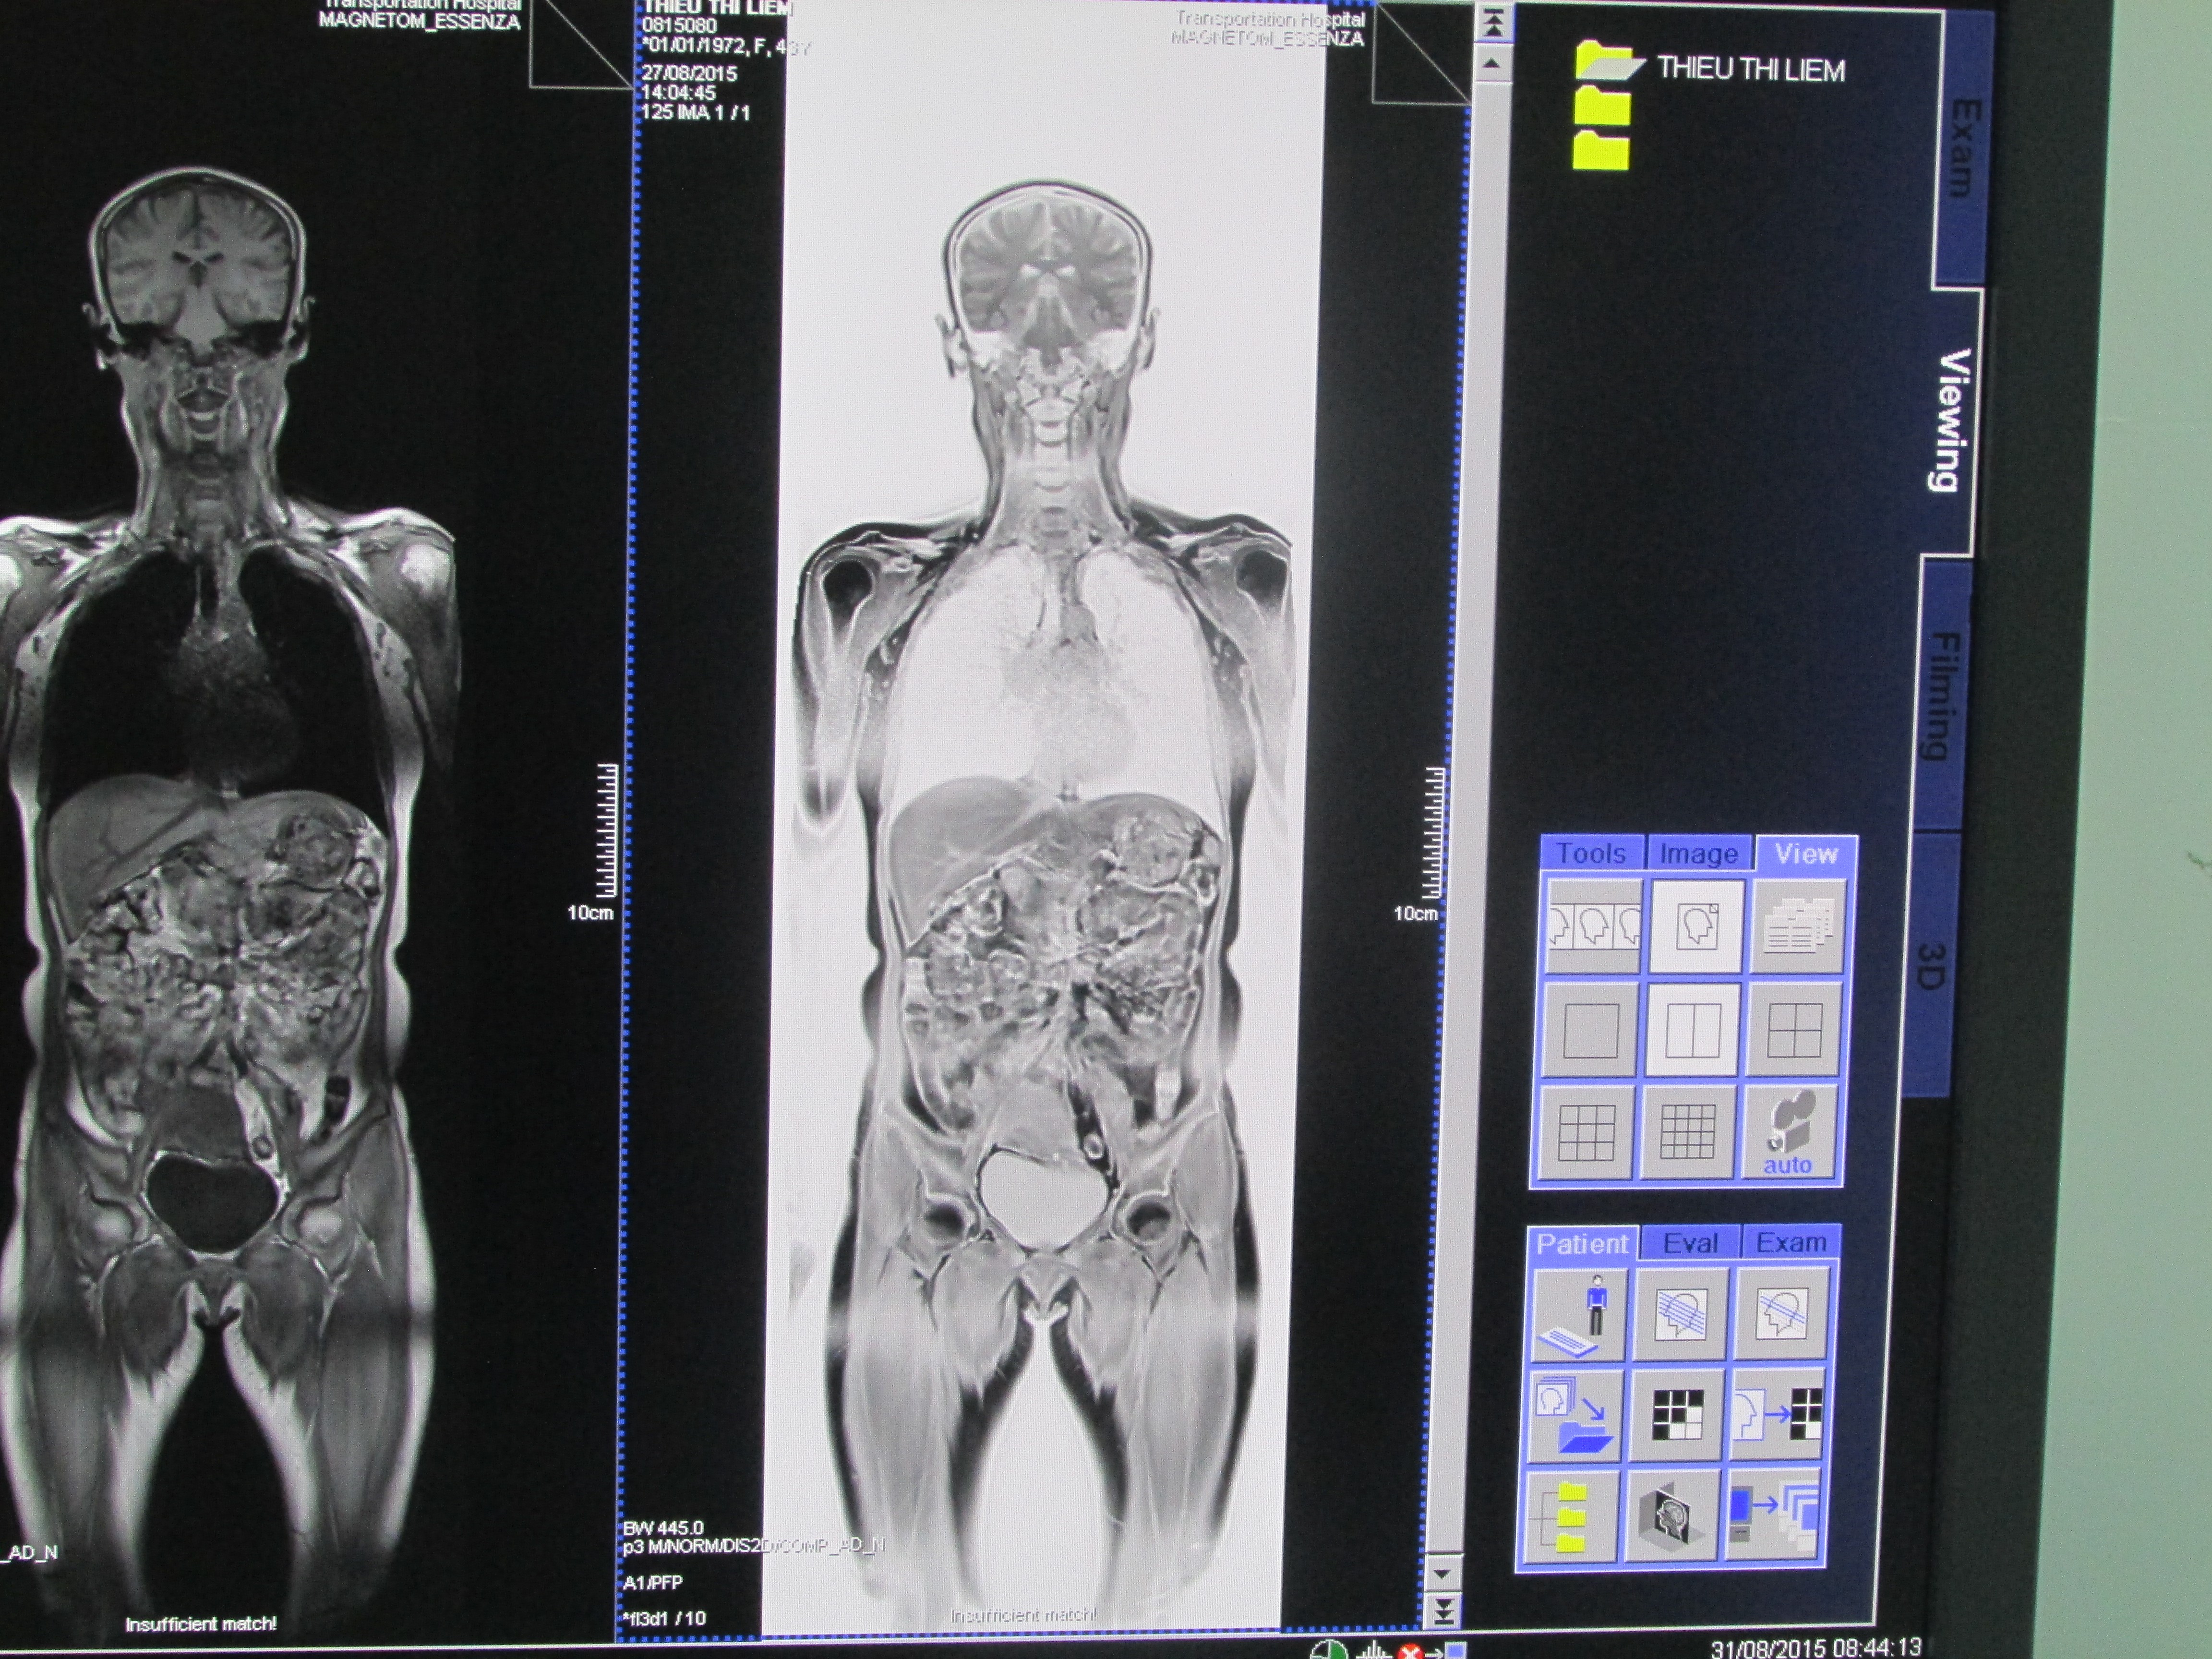

- Cùng với sự phát triển về mặt tổ chức nhân sự, trang thiết bị của khoa cũng dần được đầu tư và phát triển. Từ chỗ khoa chỉ có máy X-Quang nửa sóng, máy cả sóng(D 350, shimazu) đến nay khoa đã có tương đối đầy đủ trang thiết bị của chuyên ngành CĐHA như: máy X-Quang kỹ thuật số, máy chụp mạch C-Arm, máy CT-Scanner, máy siêu âm 2D, 3D, 4D. Với nguồn vốn ODA bệnh viện đã xây dựng ngôi nhà 11 tầng, khoa được trang bị các thiết bị hiện đại như máy CT-Scanner 16 lớp, máy MRI 1,5 tesla có phần mềm tầm soát ung thư ….Các kỹ thuật trong khoa phát triển từ các kỹ thuật X-quang thường quy, X-quang KTS ..SA 3D, 4D, siêu âm đàn hồi mô, Chụp mạch can thiệp, đến các kỹ thuật cao như MRI, CT - Scanner sọ não, ổ bụng.....Đặc biệt là MRI toàn thân tầm soát ung thư và phân độ TMN. Hiện nay khoa là một trong những địa chỉ tin cậy của người bệnh trong, ngoài ngành GTVT và người dân trong khu vực.

- Thăm khám MRI các bộ phận, đặc biệt MRI toàn thân tầm soát ung thư và phân độ TMN.

- Đặc biệt thực hiện kỹ thuật MRI toàn thân tầm soát ung thư và phân độ TMN, với kỹ thuật này đánh giá được tổn thương nguyên phát, tổn thương di căn với chi phí thấp và là phương pháp không nhiễm xạ. Cùng với PET/ CT là những kỹ thuật cao trong chẩn đoán ung thư.